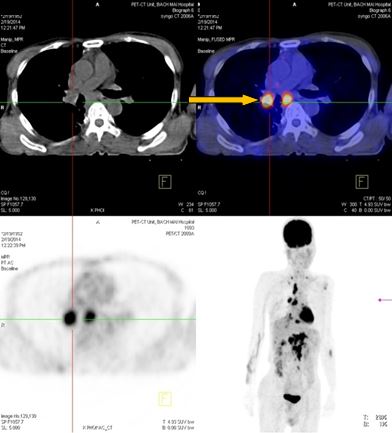

-          Bệnh nhân đã được tiến hành chụp PET/ CT đánh giá, kết quả:

+ Vùng phế quản gốc phải có khối KT 2,4x1,7cm, tăng hấp thu F-18 FDG, max SUV=8,50. Hạch trung thất kích thước lớn nhất 3,1x3,5cm, max SUV=10,29

- Trước điều trị: Khối u 2,4x1,7cm, max SUV=8,50. Hạch dưới carina KT 3,1x3,5cm, max SUV=10,29

- Sau điều trị 4 thángKhông rõ u, không có hạch trung thất